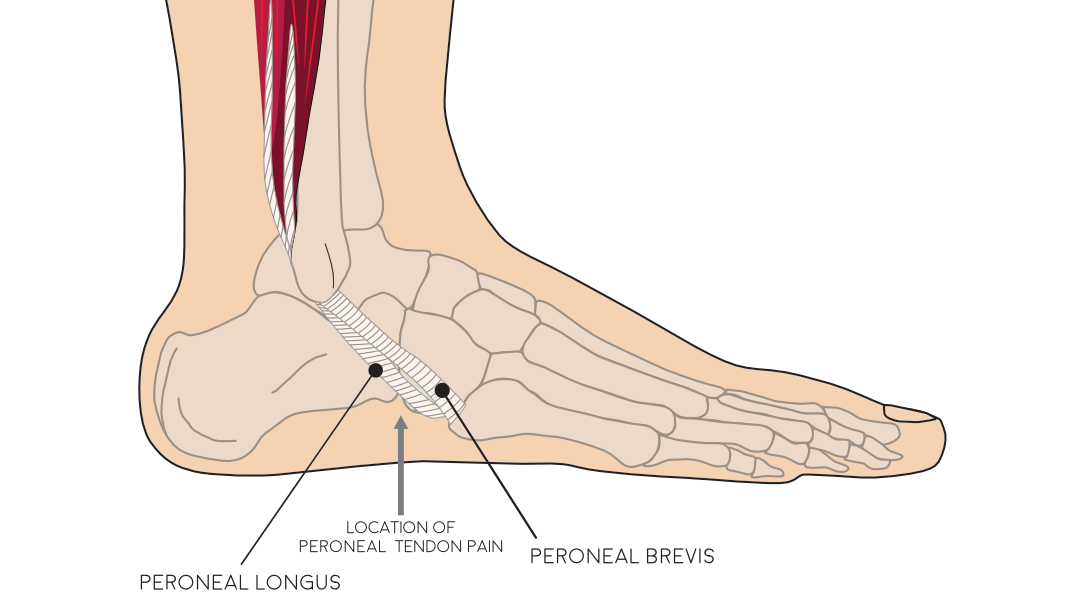

Peroneal tendonitis store, Peroneal Tendonitis FootEducation store

Peroneal Tendonitis FootEducation

Peroneal Tendon Attenuation Peroneal Tendonitis SLO Motion